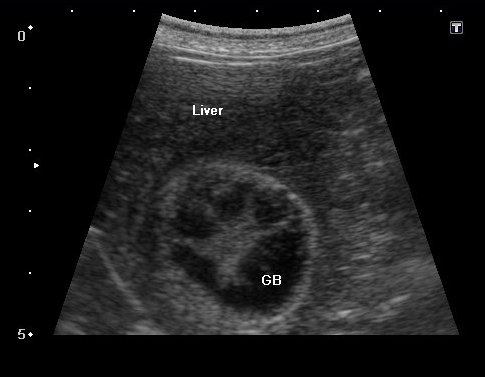

定期的な血液検査(最低年に1回)を実施し、肝酵素等が上昇していれば胆嚢のエコー検査をします。

胆嚢粘液嚢腫の場合、エコー検査では放射状に胆泥が胆嚢壁に付着したキウイフルーツ状の所見が見られます。

エコーで胆嚢炎と胆嚢粘液嚢腫であることを確認し、破裂の危険性 を考えて腹腔鏡下胆嚢摘出術を実施することになりました。